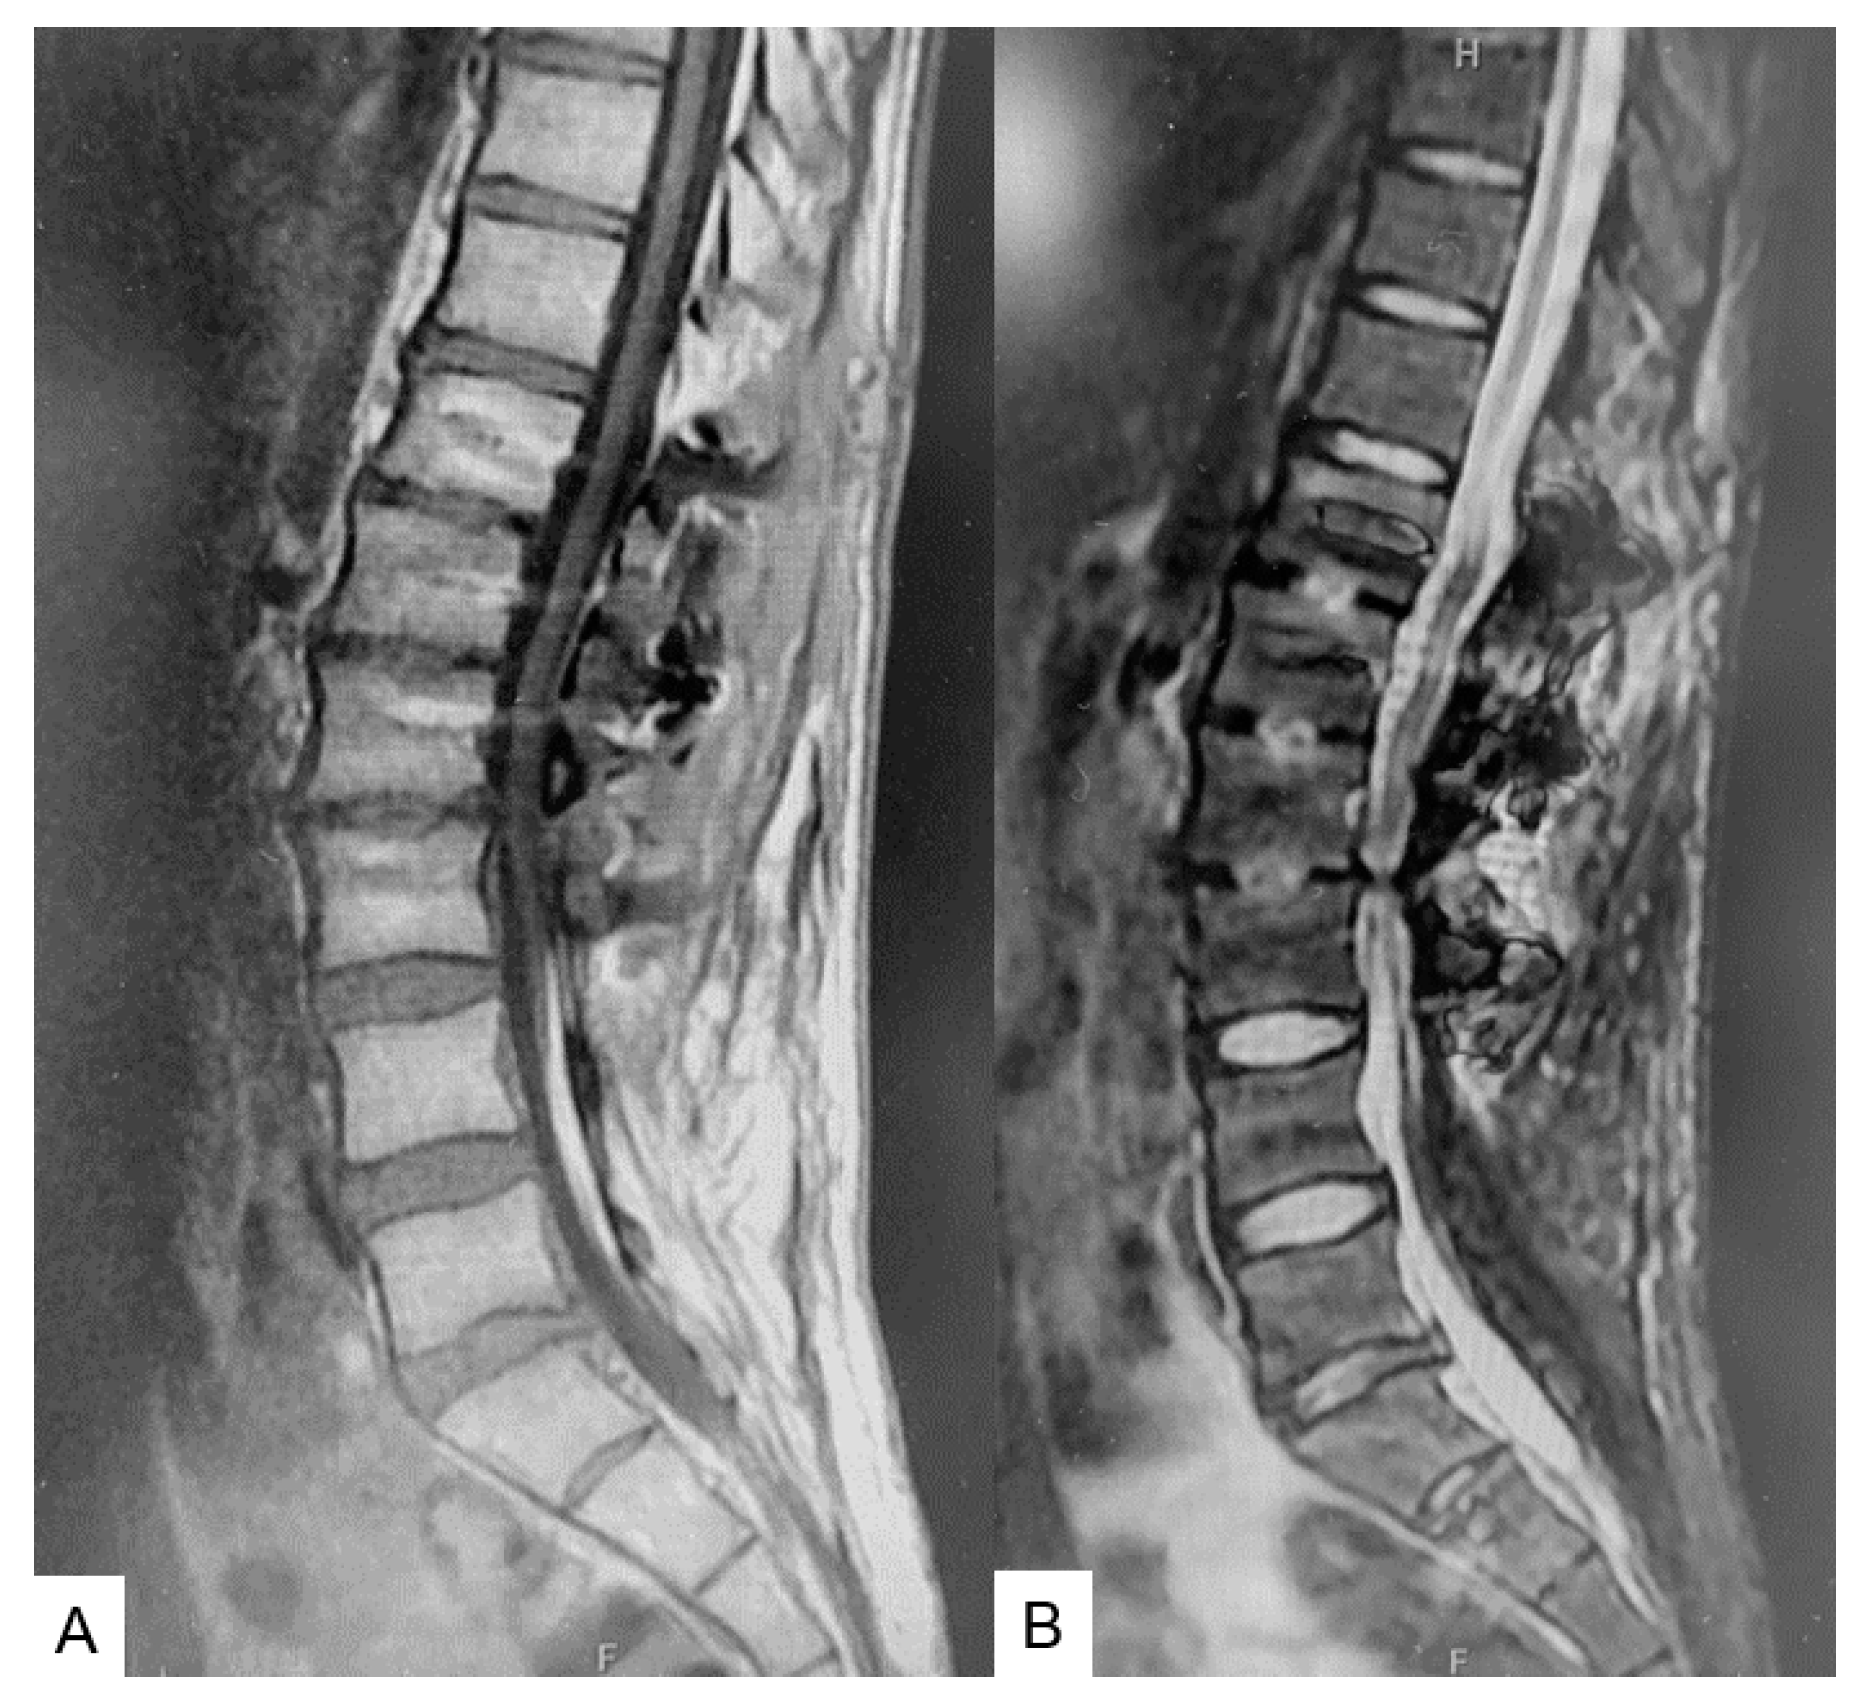

2.3. Preoperative Imaging

2.4. Surgery